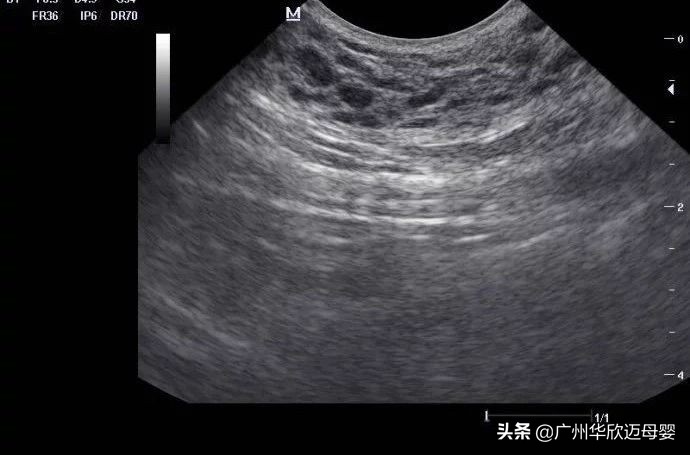

产检项目:腹部B超

1.这个时间段的检查,主要是为了确定宫内孕。所以孕2月的B超检查是有必要的。

2.可能有些医院的医生或者护士粗心大意,会误把腹部B超当成了阴超。然而孕早期的 阴超,极容易造成出血流产。所以我们应该拒绝阴超,去检查的时候自己应该留个心眼。